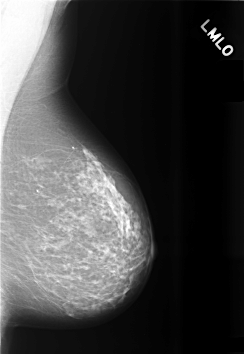

C_0473_1.LEFT_MLO

LEFT_MLO LINES 5664 PIXELS_PER_LINE 3896 BITS_PER_PIXEL 12 RESOLUTION 50 NON_OVERLAY